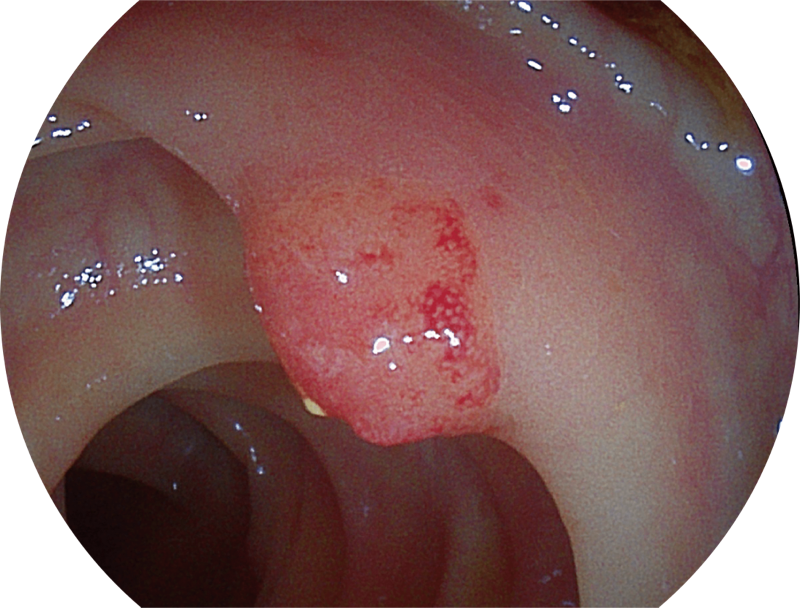

百万级像素高清传感器,1080P全高清视频信号输出,图像清晰。

能够凸显黏膜浅层和中层血管轮廓,适用于中、远景观察下的病灶识别和早癌筛查。

能够凸显黏膜浅层血管轮廓和黏膜表面微结构,适用于中、近景观察下的早癌精确诊断。